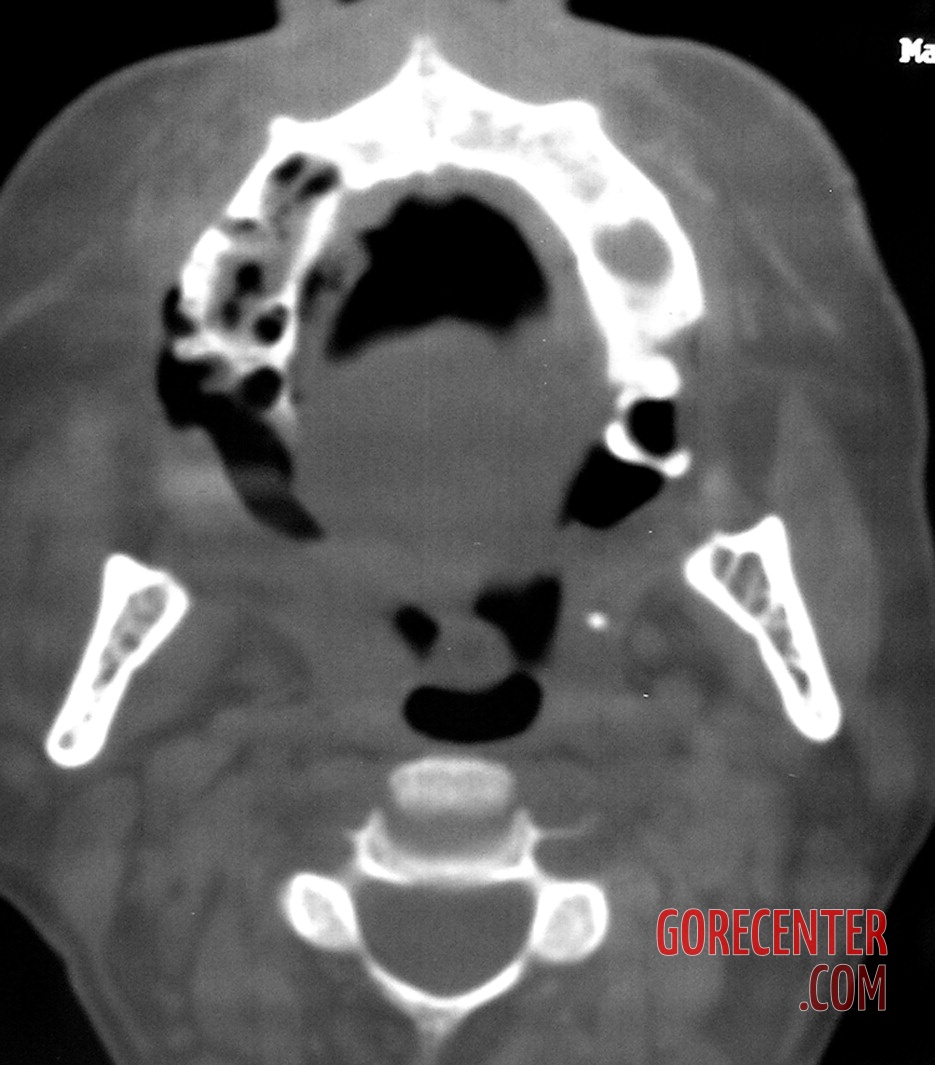

Further examinations, including blood tests, did not reveal diabetes or other common conditions that could explain the symptoms. However, it was evident that the body was fighting a severe infection. A crucial turning point came with a CT scan, which revealed extensive damage to the maxillary bone and spread of inflammation into the paranasal sinuses, including the deeper ones. Fortunately, the brain and eye sockets were not yet affected.